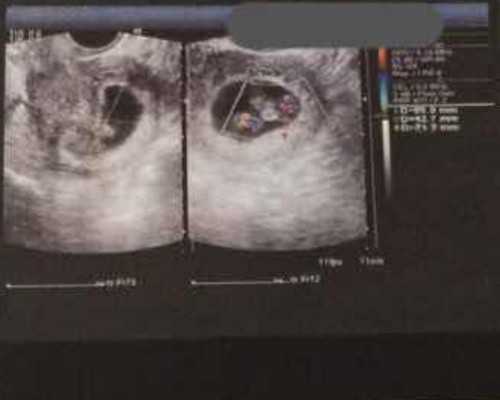

1.阴道超声检查

对卵巢进行影像学检查,以监测卵泡的发育即卵成熟的充满卵子的卵巢囊。